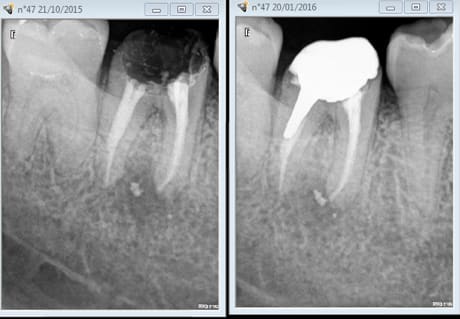

Ici en core + ic provisoire labo sur RTE ( on sort d'une pèche maous costaud) la définitive dans 6 mois.

Capture d e cran 2016 01 20 09.36 - Eugenol

Capture d e cran 2016 01 20 09.37 - Eugenol